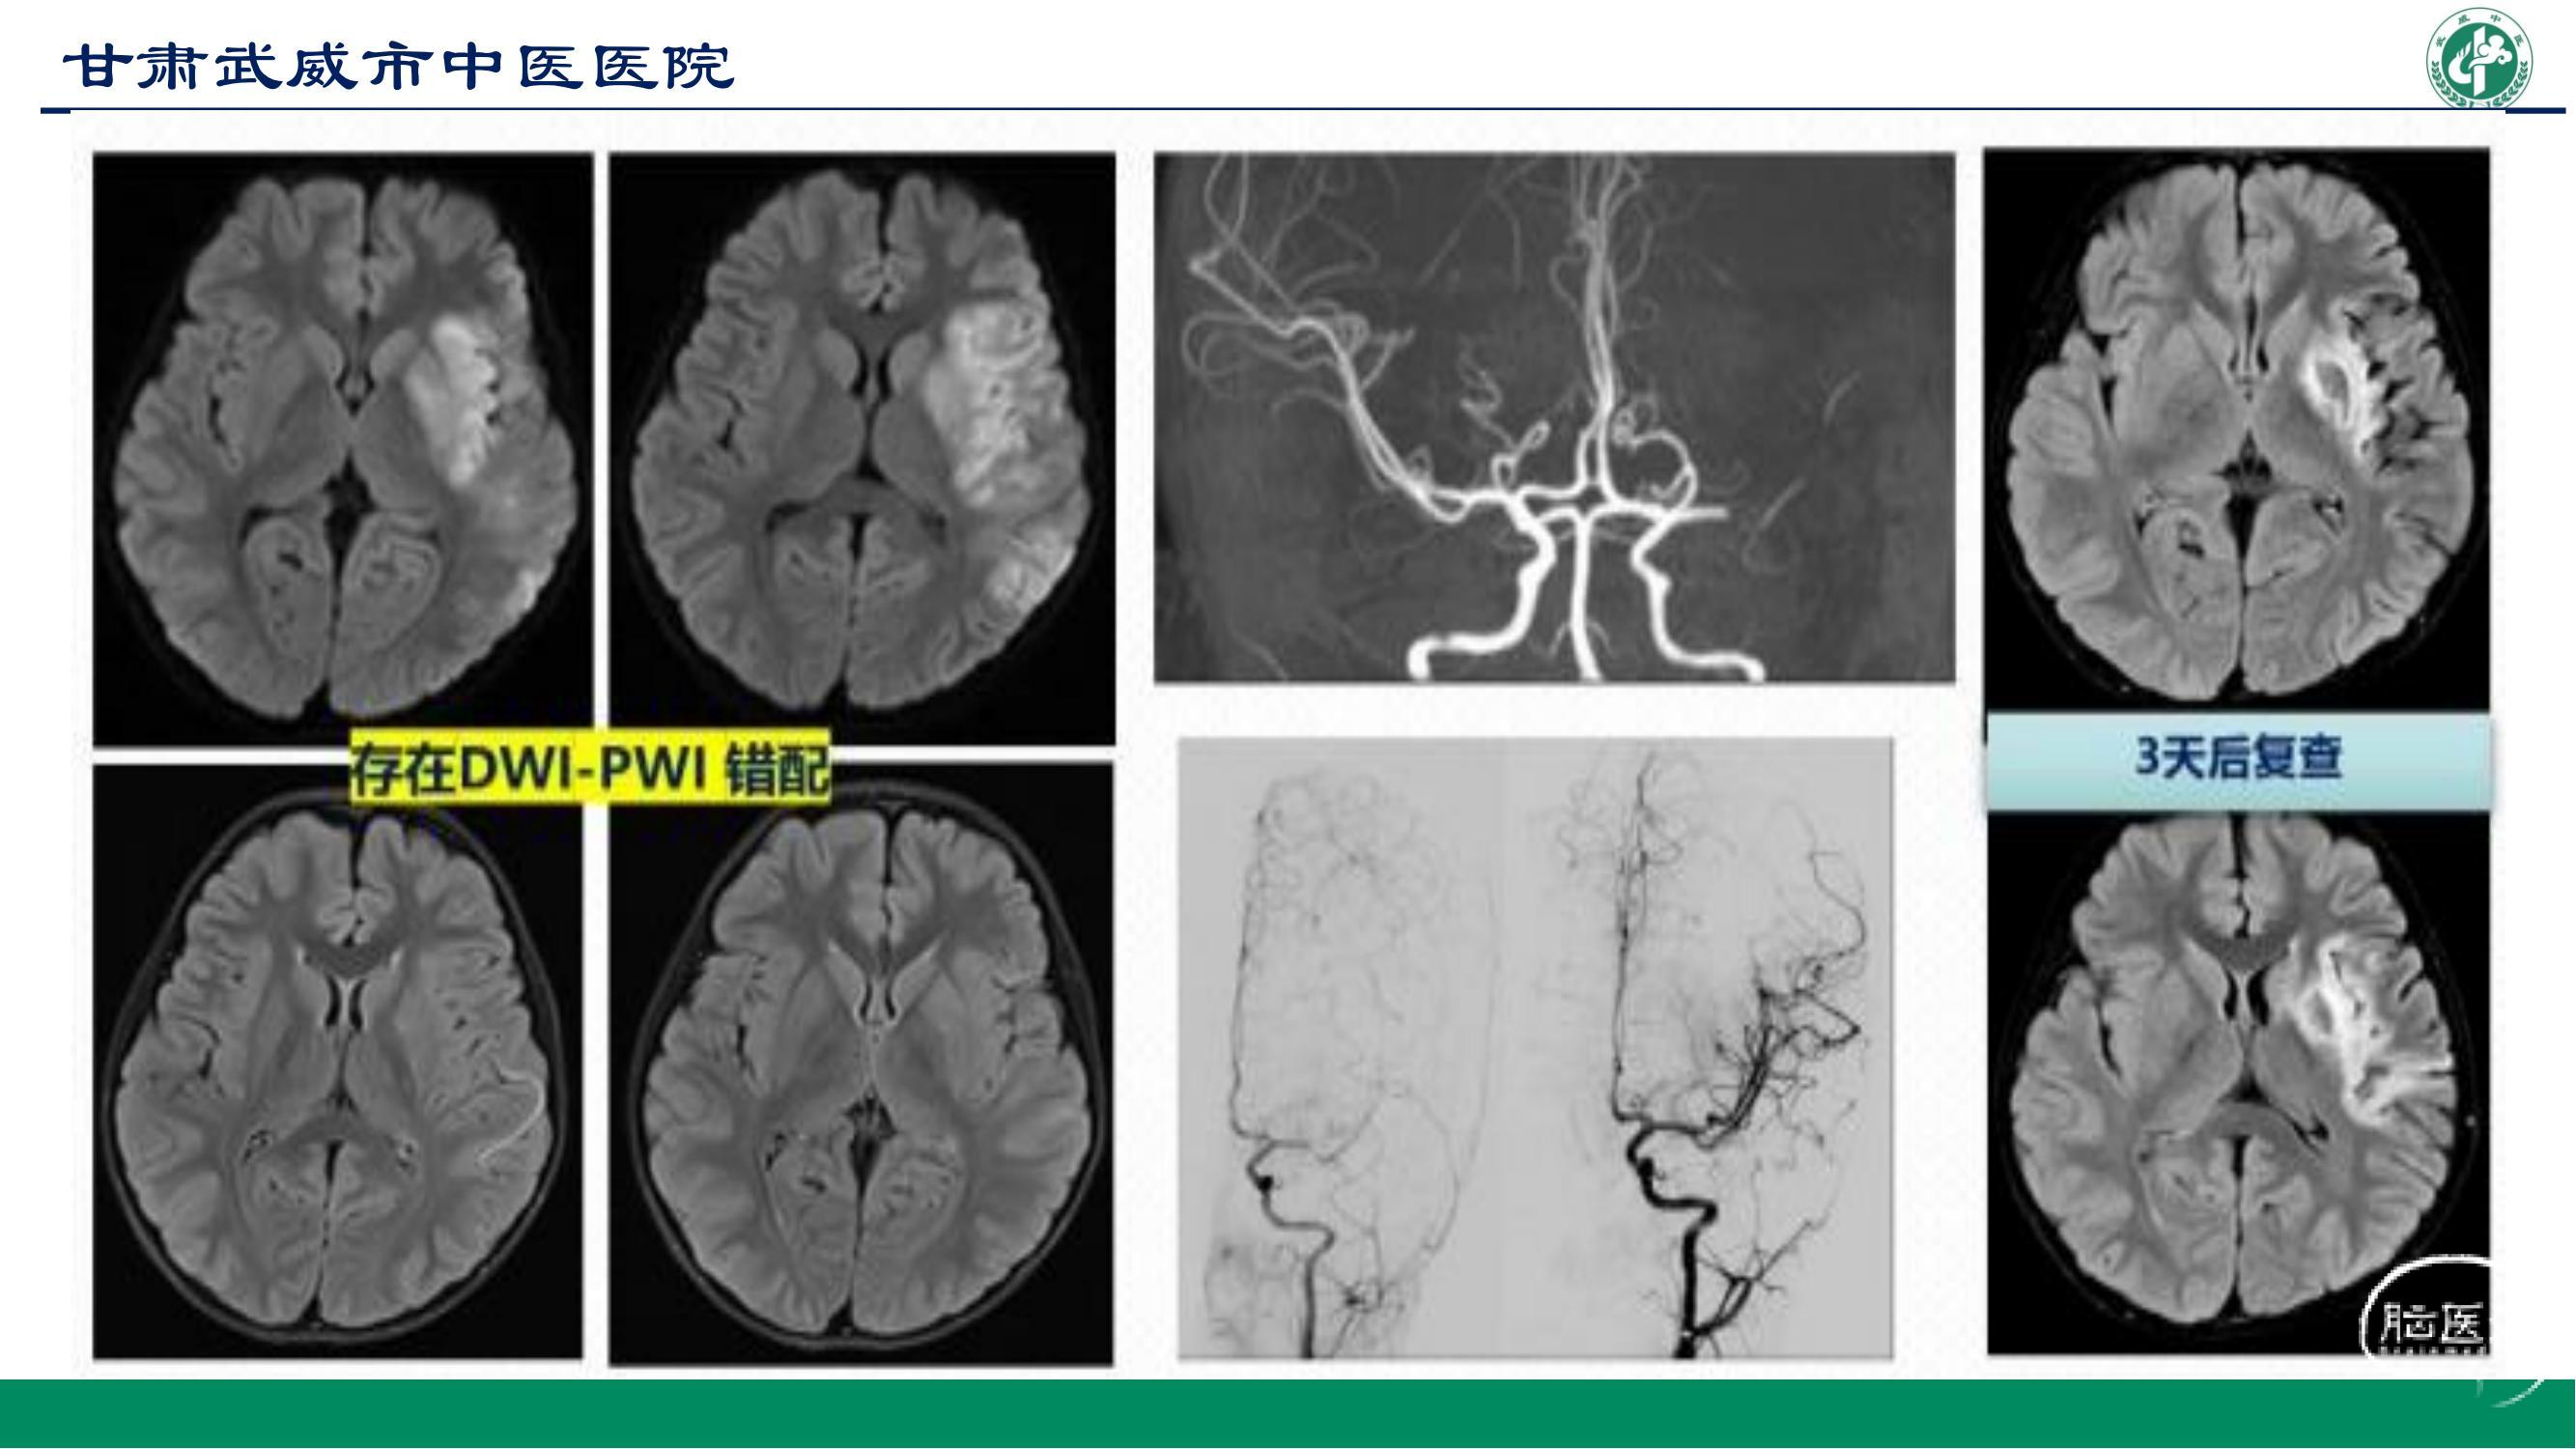

主任医师。 武威市中医医院脑病科主任。甘肃省陇原人才,武威市中医院脑血管介入团队学科带头人,武威市脑血管介入与卒中早期康复创新工作班组组长。 从事神经内科工作20余年,曾在兰大二院进修神经内科和急诊,中国人民解放第940医院神经内科高级卒中中心、陆军军医大附属新桥医院高级卒中与介入中心学习脑血管介入。 任武威市老年病专业委员会主任委员、武威市中西医结合神经内科专业委员会副主任委员、武威市中西医结合眩晕专业委员会副主任委员、武威市神经内科学会常务委员、甘肃省脑血管专业委员会委员。 开展脑出血微创锥颅引流近500余例,经桡动脉脑血管造影500余例,开展急性脑梗塞血管内机械取栓,动、静脉桥接、颈内动脉狭窄、椎动脉狭窄、锁骨下动脉狭窄或闭塞的血管支架成形术。